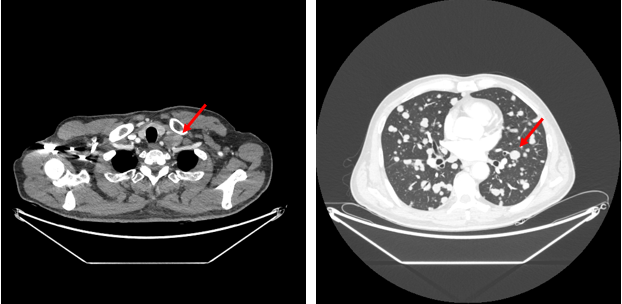

2022年6月2日胸部增强CT:双肺及左锁骨下多发占位,考虑转移。

图1.胸部CT

从指南可以看出,HER2阳性胃癌是一类特殊的疾病亚型,需抗HER2治疗。并且免疫联合化疗目前在晚期胃癌或可考虑全人群推荐。该患者为HER2阳性胃癌伴腹腔淋巴结、腹膜后淋巴结、左锁骨上淋巴结、肺、肝多发转移。给予曲妥珠单抗靶向治疗+抗PD-1单抗免疫治疗+XELOX方案化疗4周期后取得了PR的状态,肺上的病灶几乎消失,转移淋巴结也有了非常明显的缩小。CA199从初治前的5413U/ml恢复到正常范围。

本例患者是1例晚期HER2阳性胃癌,伴有多处淋巴结、肺、肝转移,经过信迪利单抗+曲妥珠单抗(汉曲优)+XELOX方案化疗4周期后疗效评价达到PR,肺上的病灶几乎消失,转移淋巴结也有了非常明显的缩小。治疗过程中仅观察到胃肠道反应,心脏、肝肾功能毒性及免疫治疗相关毒性均未出现。证实了化疗联合汉曲优和抗PD-1单抗对晚期HER2阳性胃癌疗效和安全性。